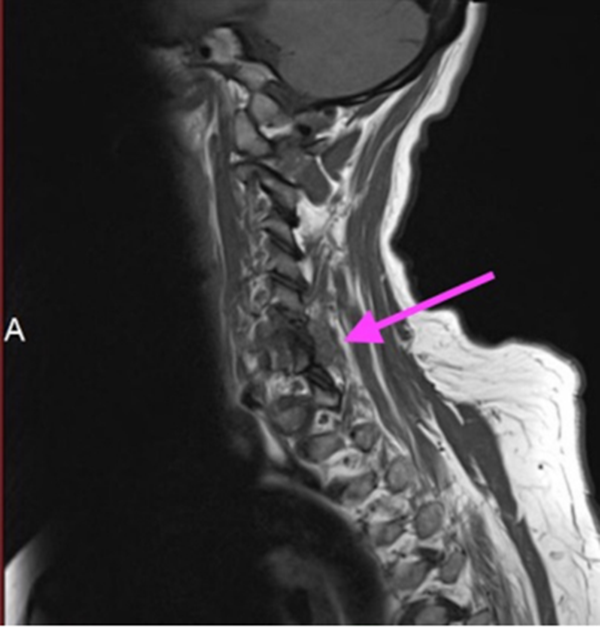

颈椎焦磷酸钙沉积病

C6/7椎板关节面不规则,骨髓信号减弱,椎周信号改变延伸至C6神经根的后侧和C7神经根的上侧

箭头显示在椎间后关节周围和左侧C6/7神经孔内的炎症过程增强